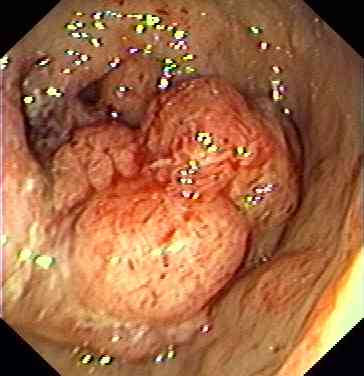

Appearance of rectal cancer.